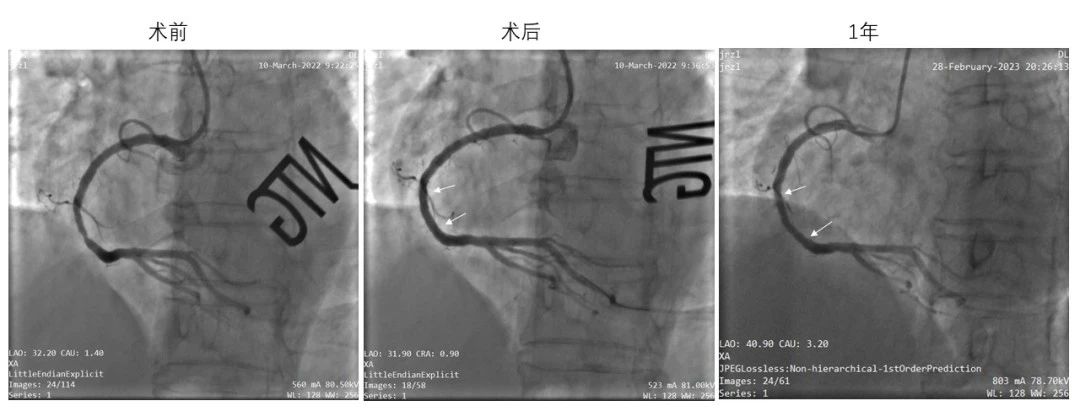

(左:术前靶病变处造影;中:IBS®支架植入后造影;右:术后1年造影,结果显示支架内通畅,未见明显狭窄)